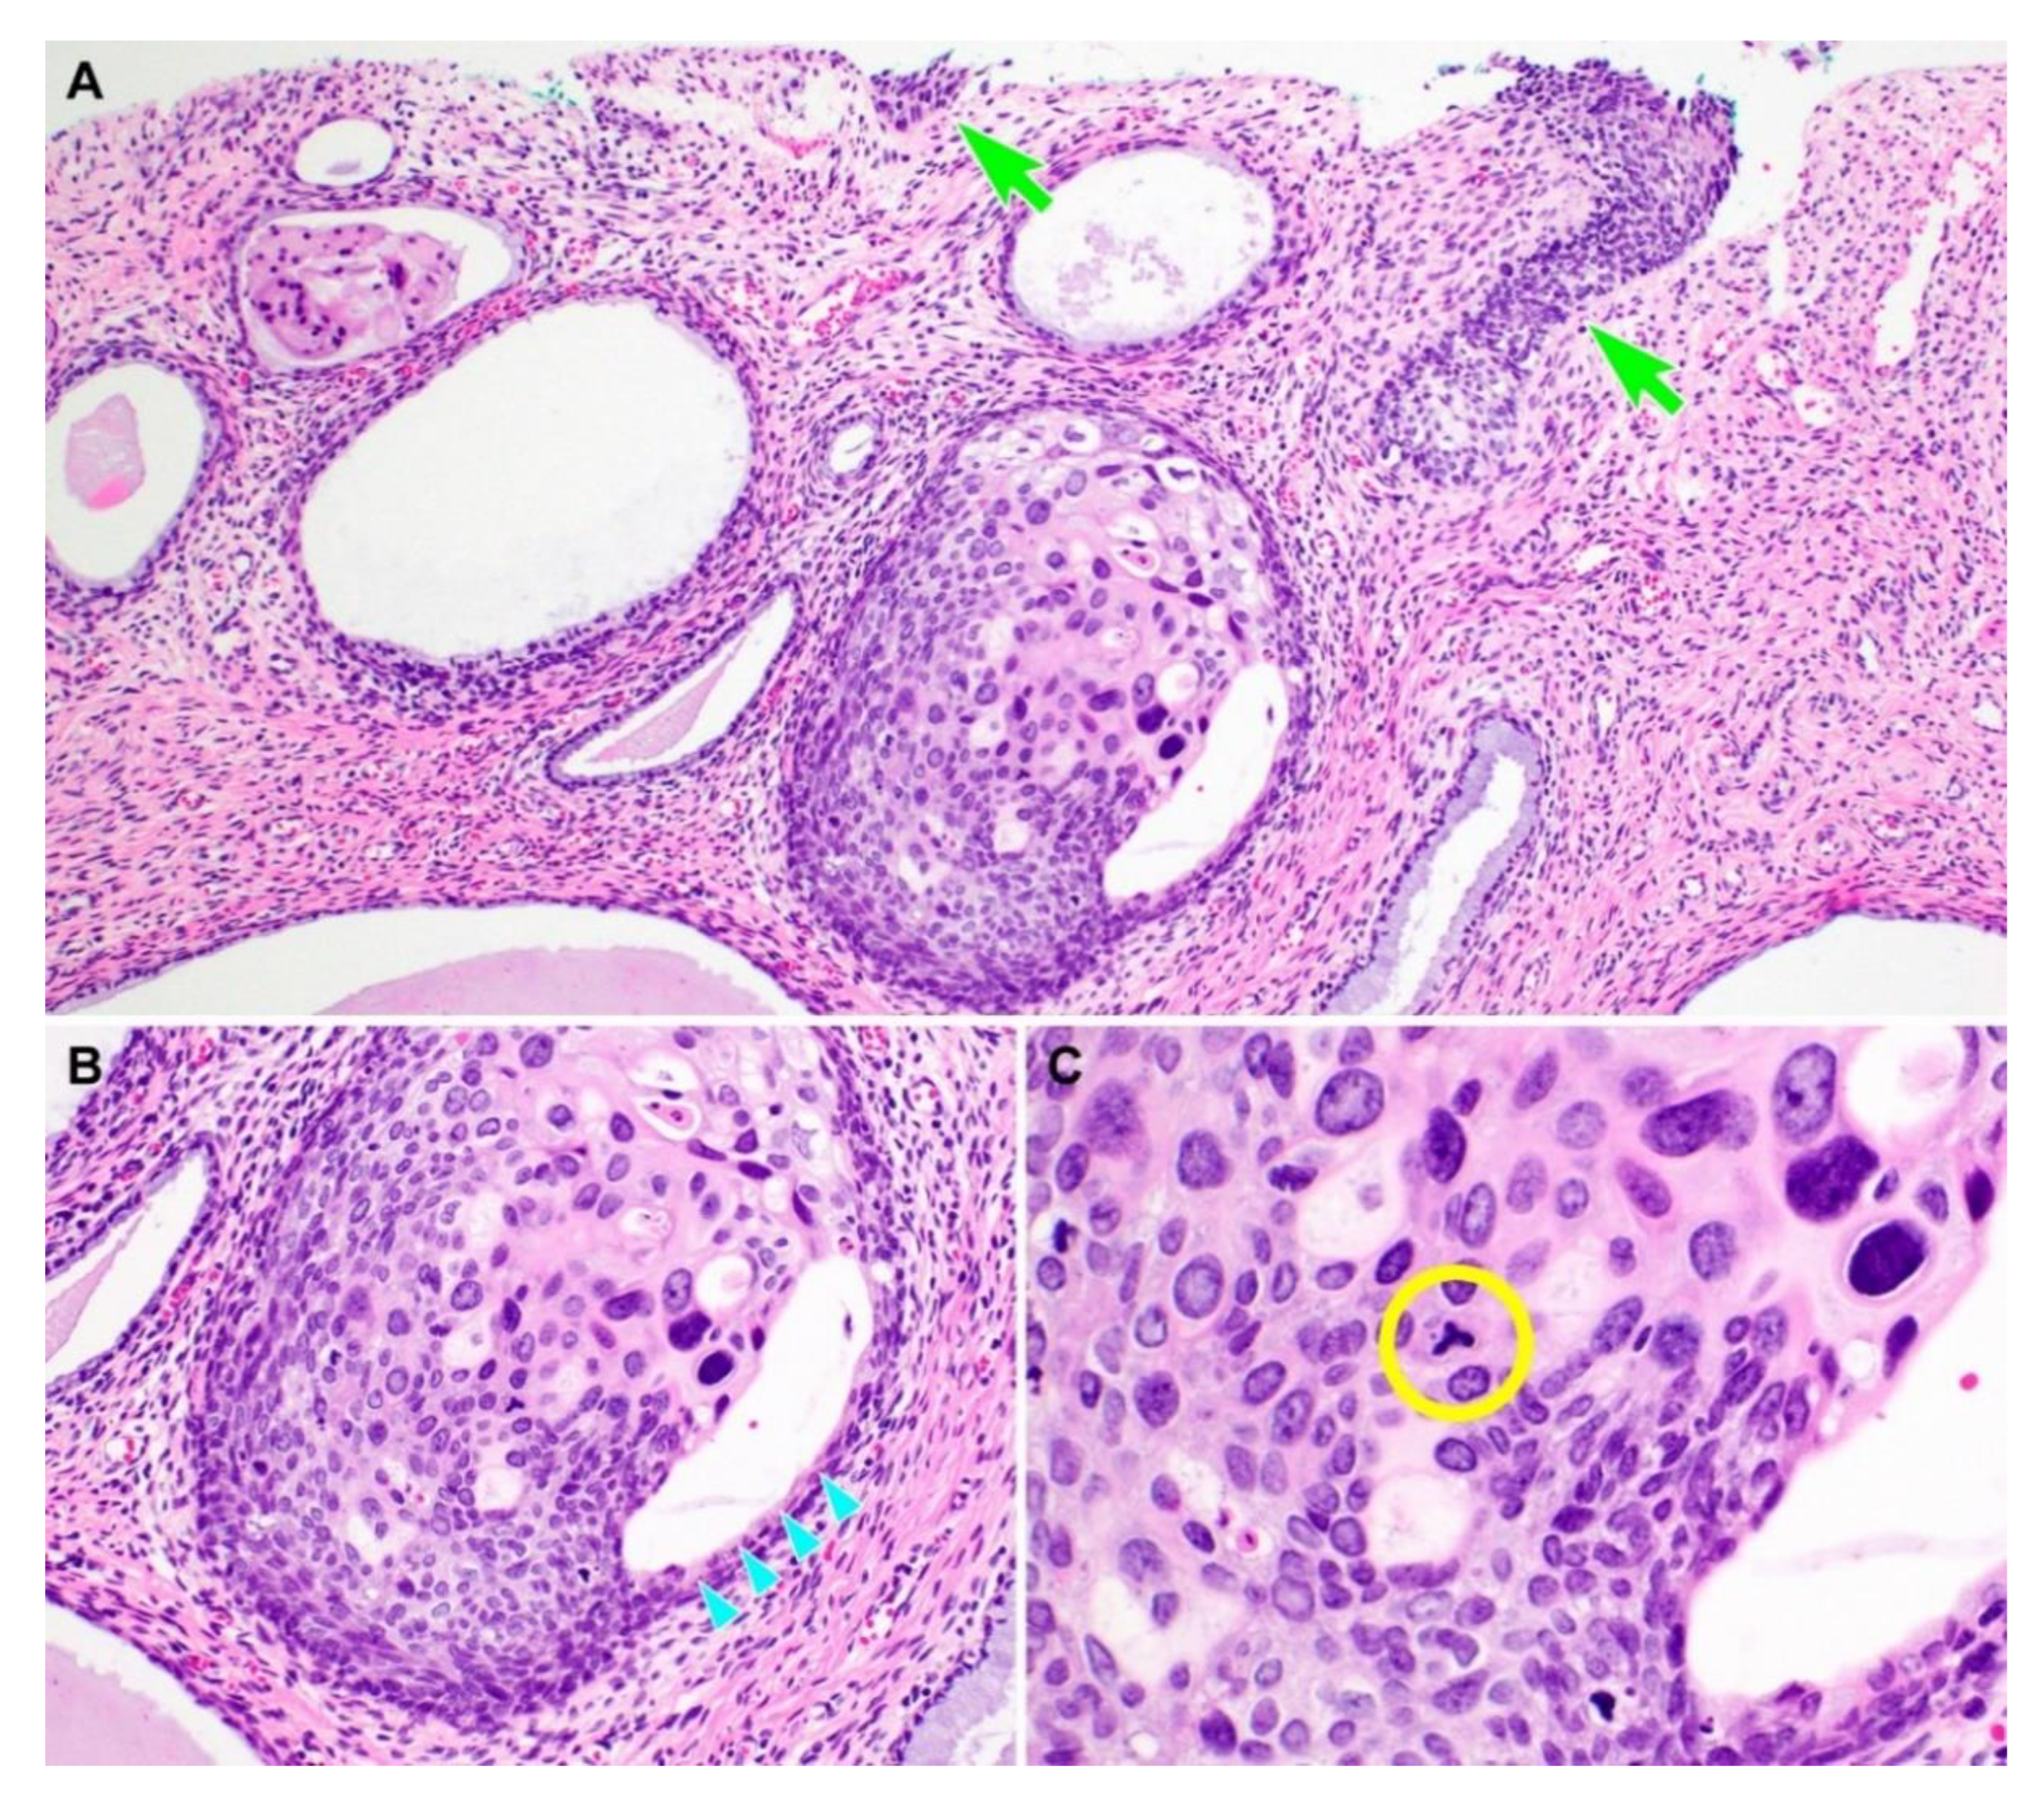

3.2. Pathological Characteristics